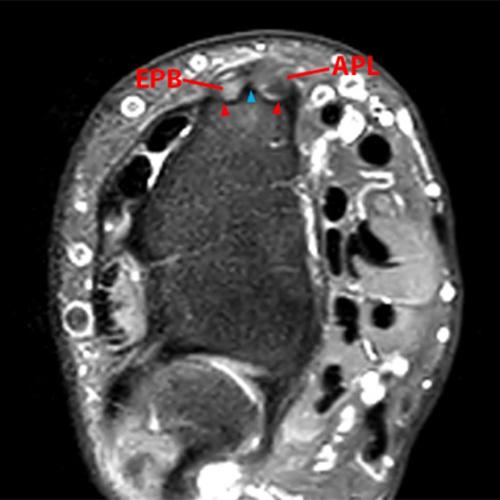

Clinical History: A 68-year-old female presents with radial-sided pain and swelling. Axial T1-weighted (1A), axial fat-suppressed proton density-weighted (1B), and coronal fat-suppressed proton density-weighted (1C) images are provided. What are the findings? What is your diagnosis?

Figure 2: The axial T1-weighted (2A), axial fat-suppressed proton density-weighted (2B), and coronal fat-suppressed proton density-weighted (2C) images demonstrate a thickened extensor retinaculum, surrounding soft tissue edema, and fluid signal in the first extensor compartment of the wrist (arrowheads). Marrow edema is noted within the subjacent radius (asterisks). A single extensor pollicis brevis and two abductor pollicis longus tendon slips are present with heterogeneous intrinsic signal.